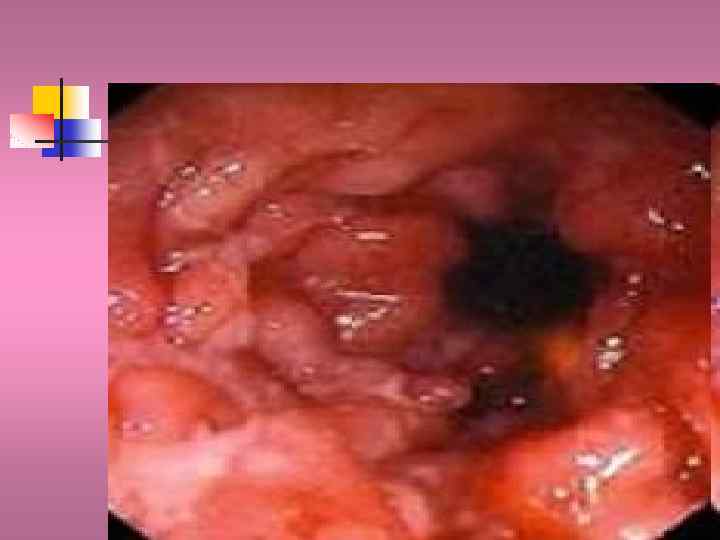

Неспецифический язвенный колит

Неспецифический язвенный колит